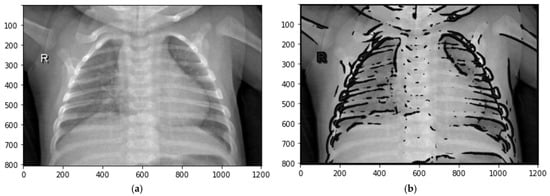

where s > 0. See Figure 6.

Figure 6.

Transformations of local contrasts based on the fuzzy standard deviation of brightness values: (a) original image; (b) defuzzified image.